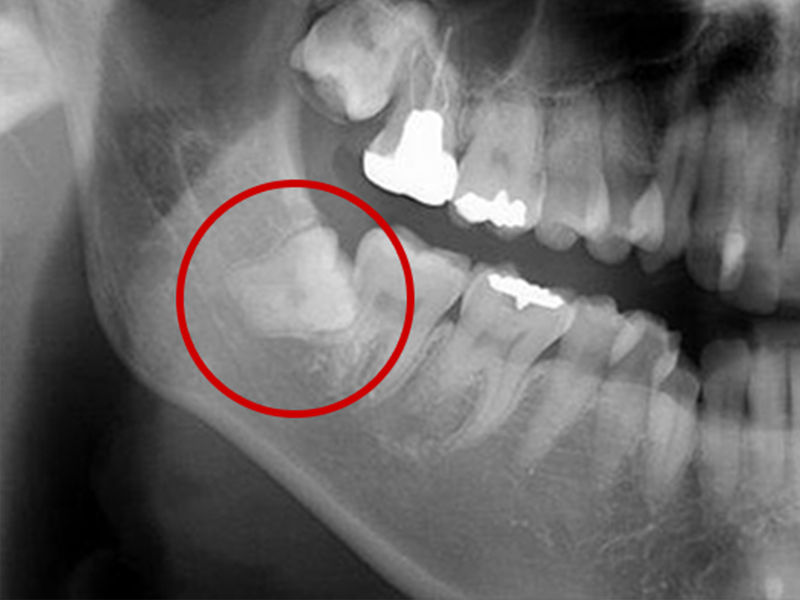

親知らずとは大臼歯(大人の奥歯)の中で一番後ろに位置する第3大臼歯です。

智歯とも呼ばれ20歳前後で生えてくることが多く、一般的には上あごの左右2本と下あごの左右2本計4本ありますが、もともと親知らずのない人や4本揃っていない人など、個人差があります。

親知らずは横や斜めに生えてきたり、歯ぐきがかぶっていることがあります。そのため親知らずの周囲には細菌が残りやすく、トラブルを起こし、痛みの原因になります。

親知らずが周囲に以下のような悪影響をもたらしている場合は、早めの抜歯をおすすめします。

- 親知らずの隣の歯がむし歯になる

- 親知らずの周りの歯ぐきが腫れる(智歯周囲炎)

- 生えてきた親知らずが、頬や歯ぐきの粘膜を傷付け口内炎となる

- 親知らずがかみ合わせに影響を与え、顎関節症になる

- 歯が押されて歯ならびが変わってしまう